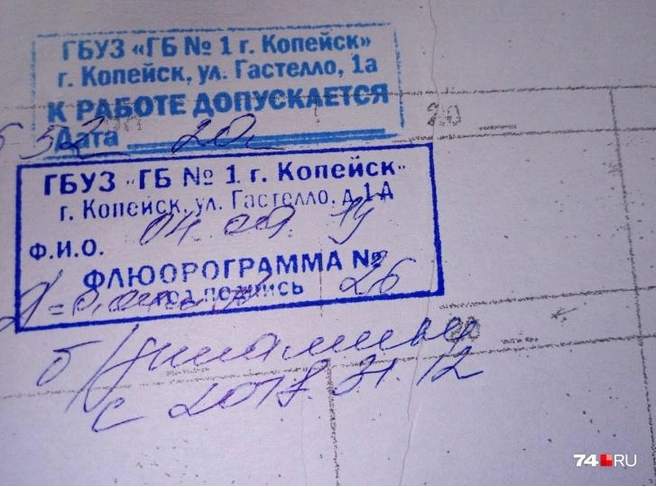

Фотографии рентгеновских снимков без необходимости направления от врача